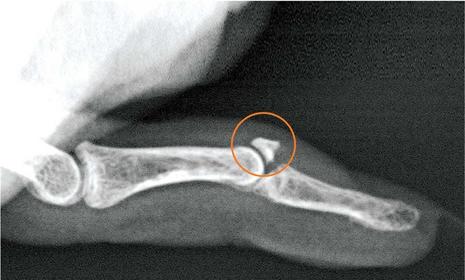

Baseball (Mallet) Fx

Why would you perform any of the 4, or all 4 of the radial head lateral views? To view occult Fx's of the radial head or neck

Which projection/position best demonstrates occult fractures or the radial head or neck? any 4 of the Radial Head Laterals